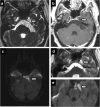

Meckel's cave is a dural recess in the posteromedial portion of the middle cranial fossa that acts as a conduit for the trigeminal nerve between the prepontine cistern and the cavernous sinus, and houses the Gasserian ganglion and proximal rootlets of the trigeminal nerve. It serves as a major pathway in perineural spread of pathologies such as head and neck neoplasms, automatically upstaging tumours, and is a key structure to assess in cases of trigeminal neuralgia. The purpose of this pictorial review is threefold: (1) to review the normal anatomy of Meckel's cave; (2) to describe imaging findings that identify disease involving Meckel's cave; (3) to present case examples of trigeminal and non-trigeminal processes affecting Meckel's cave.

Teaching points: • Meckel's cave contains the trigeminal nerve between prepontine cistern and cavernous sinus. • Assessment is essential for perineural spread of disease and trigeminal neuralgia. • Key imaging: neural enhancement, enlargement, perineural fat/CSF effacement, skull base foraminal changes.